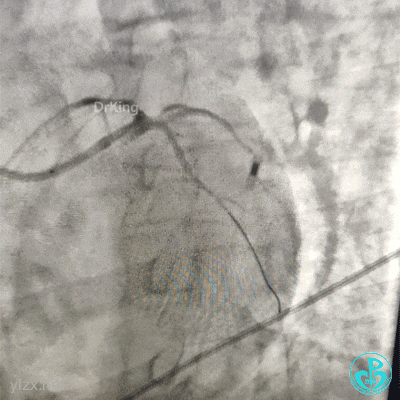

植入4.0×13mm支架1枚。

交换导丝后扩支架网眼。

结束手术。

下台时血压127/78mmHg,心率75次/分。